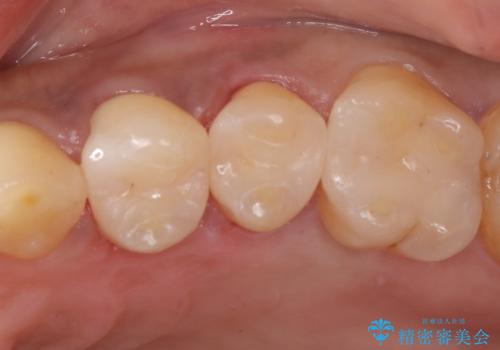

- 前医で治療された詰め物の部分に、定期検診で虫歯が見つかったため、セラミックインレーにて修復治療を行いました。

接着時にはラバーダム防湿を行っています。